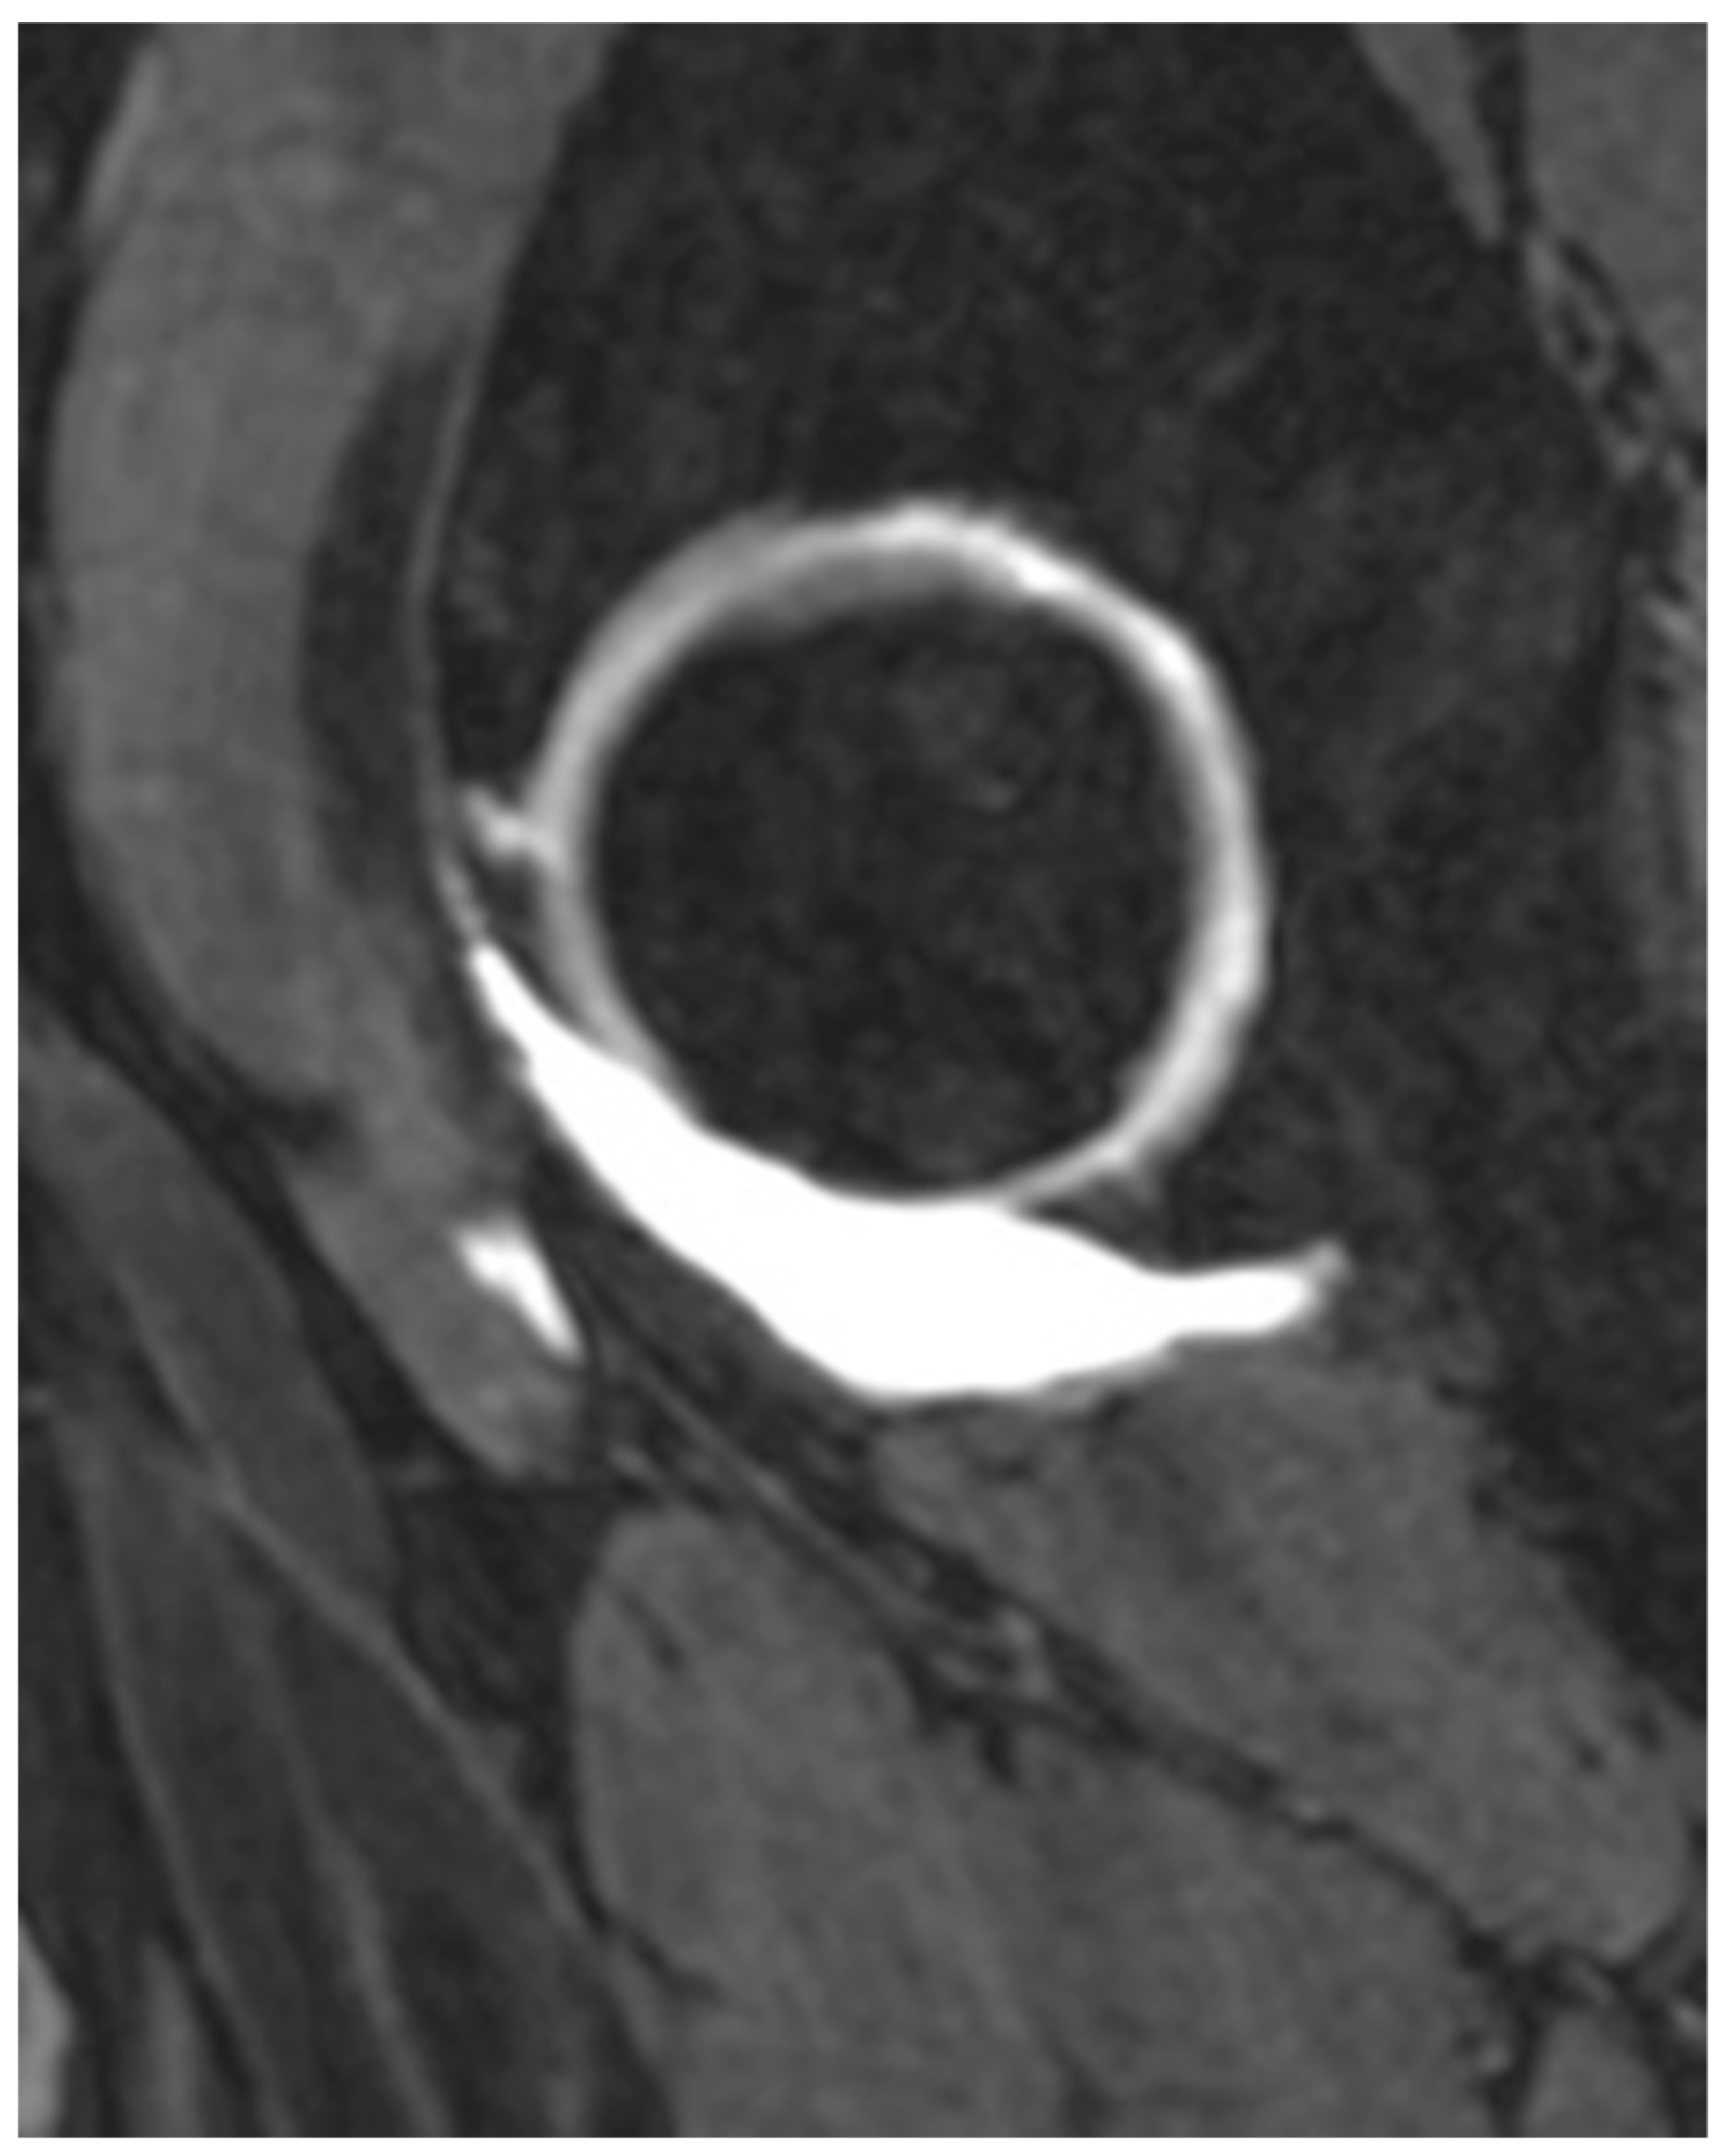

2.2. Indications